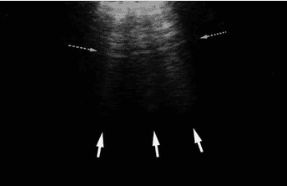

B lines are vertical hyperechoic artifacts originating from the pleural line that look similar to comet-tails. The artifact that generates B lines is the ‘ring down’ artifact.

B lines occur due to thickening of the interlobular septa, which are sheet-like structures that surround pulmonary lobules. Thickening can be due to fluid (eg. pulmonary edema, pulmonary hemorrhage), collagen fibrous tissue, or cells (eg. interstitial lung disease, sarcoidosis).

B lines are considered pathologic when there are three or more B lines in one rib space.